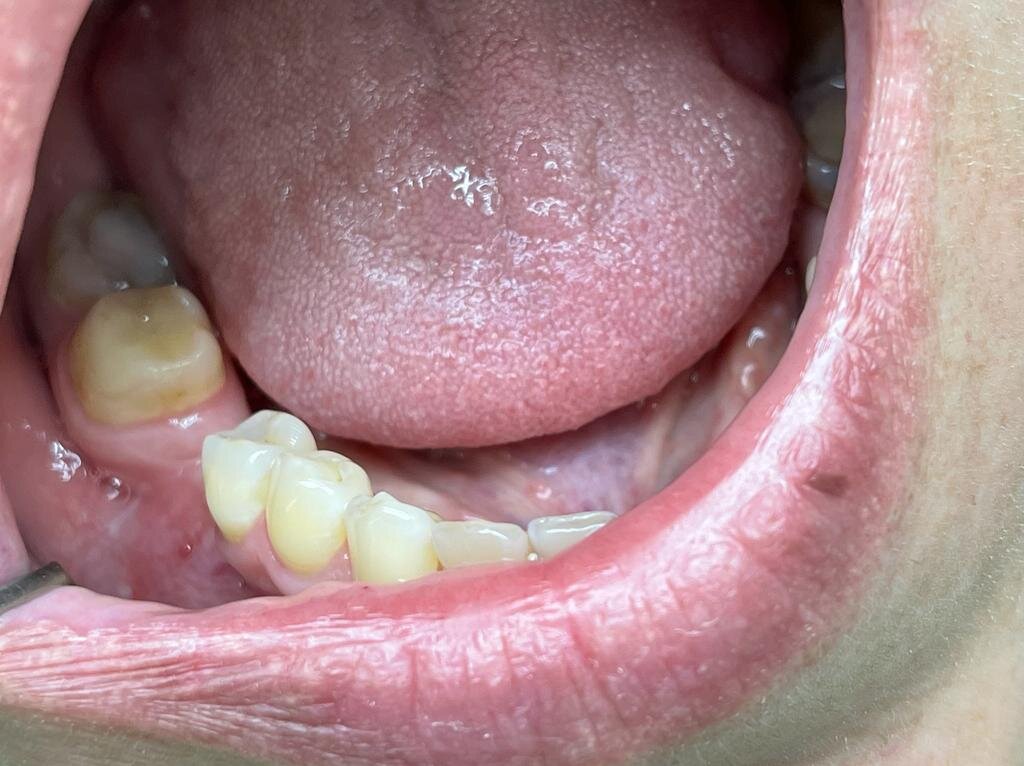

Но, что если у пациента есть десна, но ее толщина слишком маленькая. Это может привести к просвечиванию абатмента (вид синюшной десны) либо к нарушению эстетики (впалая десна).

Впалая десна